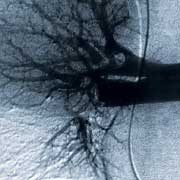

The angiography - The scintigraphy

Pulmonary ANGIOGRAPHY and VENTILATION/PERFUSION SCANNING enter into clinical practice. Before the advent of these investigations, pulmonary embolism was mainly diagnosed... after the patient’s death.